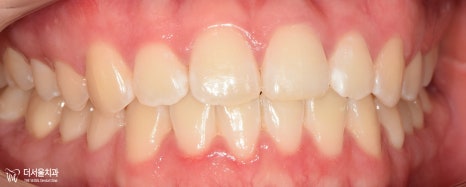

『인비절라인 기간 ’10개월’간의 기록 (초진)』

“저 입이 툭 튀어나와서 좀 집어넣고 싶어요.

근데 눈에 잘 띄는 철사들은 부담스럽더라고요.”

어?

아랫니가 윗니를 덮고 있는

‘반대교합(cross bite)’이 함께 나타나고 있군요.

정중선이 맞지 않는 것은 물론이며

전치부 치열에서 총생(crowding)도 함께 동반되었습니다.

이와 더불어,

전방으로 돌출되어 있는 모습이 관찰되네요.